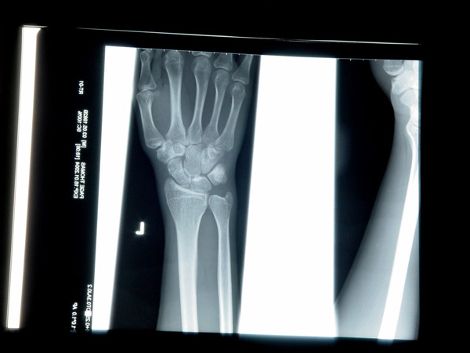

Ακτίνες Χ

Ο Γερμανός φυσικός Wilhelm Roentgen, ανακάλυψε τις ακτίνες Χ, καθώς εκτελούσε ένα πείραμα με την χρήση ενός αερόκενου σωλήνα καθοδικού ακτίνων, εφαρμόζοντας υψηλή τάση.